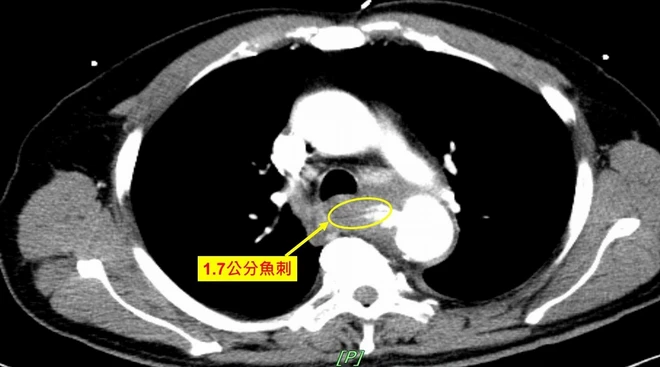

患者告吃吳郭魚時曾誤吞食1.7公分的魚刺,刺穿主動脈造成「主動脈-食道廔管」。(圖片來源:奇美醫院)

醫師檢查後發現疑似異物穿破食道,並刺穿主動脈造成「主動脈-食道廔管」,立即請急診醫師置入鼻胃管並詢問病史。患者告知1個多月前吃吳郭魚時,曾誤吞食1.7公分的魚刺,因身體無礙因此並未就醫。

由於鼻胃管洗胃為鮮紅血色,醫師研判主動脈-食道廔管併降主動脈感染性假性動脈瘤破裂,造成腸胃道大量出血,緊急執行主動脈內覆膜支架置放手術,穩定生命徵象,後續會同胸腔外科進行主動脈切除置換術、食道切除清除感染源以及第3階段的食道重建手術。